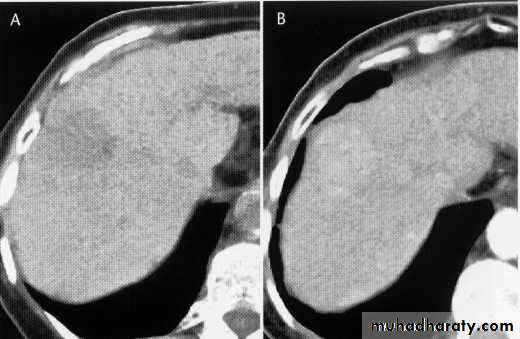

Enhanced + Unenhanced CT